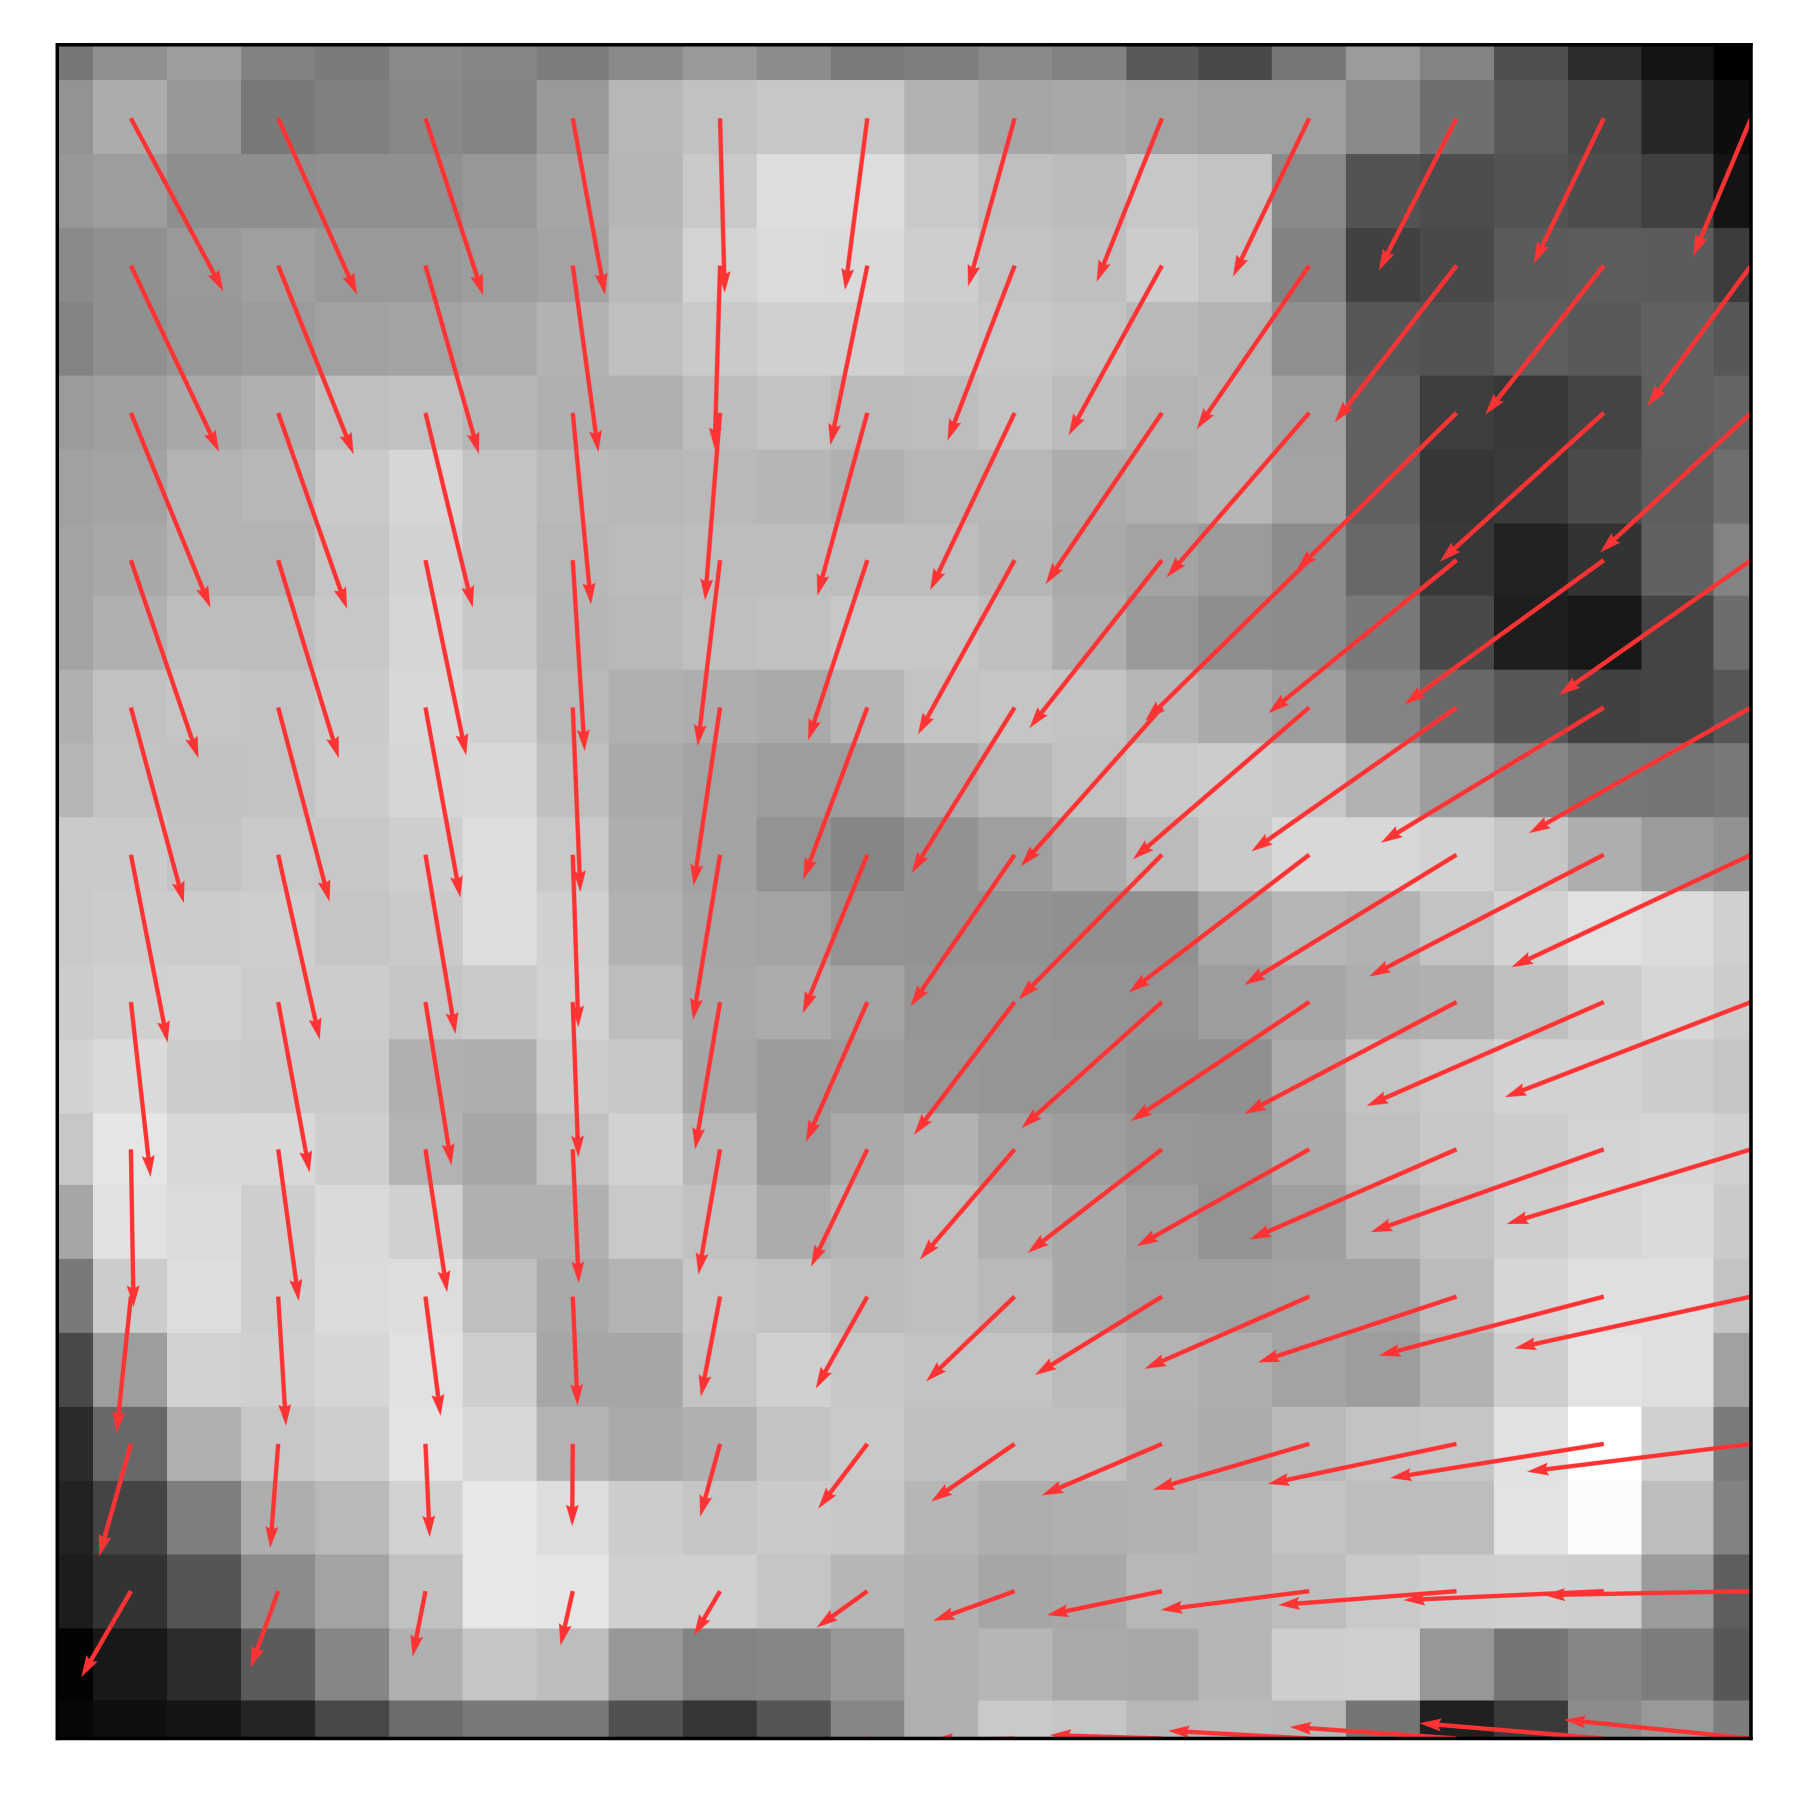

Figure 3: Visualization of motion under different continuity settings. (a) In pure discrete modeling, the motion arrow can only start from a discrete location on the image grid and linearly point toward the target location. (b) Temporal continuity allows for smooth trajectories, encoding the dynamic of the motion. (c) The proposed Continuous sPatial and Temporal modelling (CPT) allows the motion to start from any continuous location while following a smooth curve.

As illustrated in Figure 3, the continuous spatial and temporal representation leads to smooth displacement curves, starting from anywhere inside the image. As a comparison, the temporal-only continuous model allows for a smooth trajectory but limits the starting points on the grid points x03subscript𝑥0superscript3x_{0}\in\mathcal{R}^{3}italic_x start_POSTSUBSCRIPT 0 end_POSTSUBSCRIPT ∈ caligraphic_R start_POSTSUPERSCRIPT 3 end_POSTSUPERSCRIPT, illustrated in Figure 3. Besides, spatial-only contiguous models’ trajectories can start anywhere but proceed directly as in Figure 3. While the pure discrete can only model straight displacement vectors, shown in Figure 3. Equipped with properties of spatial and temporal continuity, our motion model can derive the displacement vector for any time t0(0,1)subscript𝑡001t_{0}\in(0,1)italic_t start_POSTSUBSCRIPT 0 end_POSTSUBSCRIPT ∈ ( 0 , 1 ) to any time t1(0,1)subscript𝑡101t_{1}\in(0,1)italic_t start_POSTSUBSCRIPT 1 end_POSTSUBSCRIPT ∈ ( 0 , 1 ) from any location x0subscript𝑥0x_{0}italic_x start_POSTSUBSCRIPT 0 end_POSTSUBSCRIPT using an ODE solver (such as the Euler method 42):